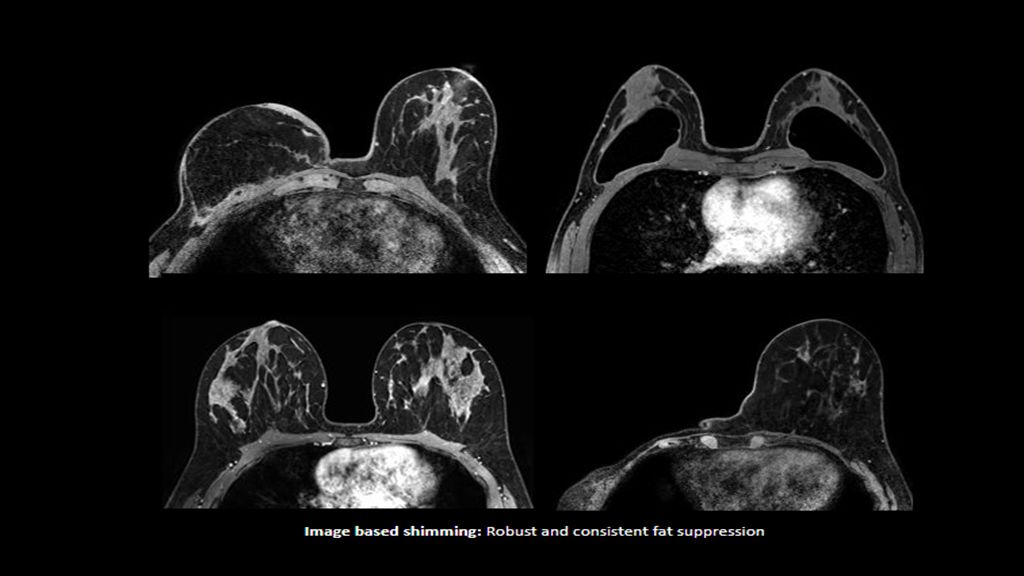

Philips - SmartSpeed Precise- Breast NMRF445C - Philips